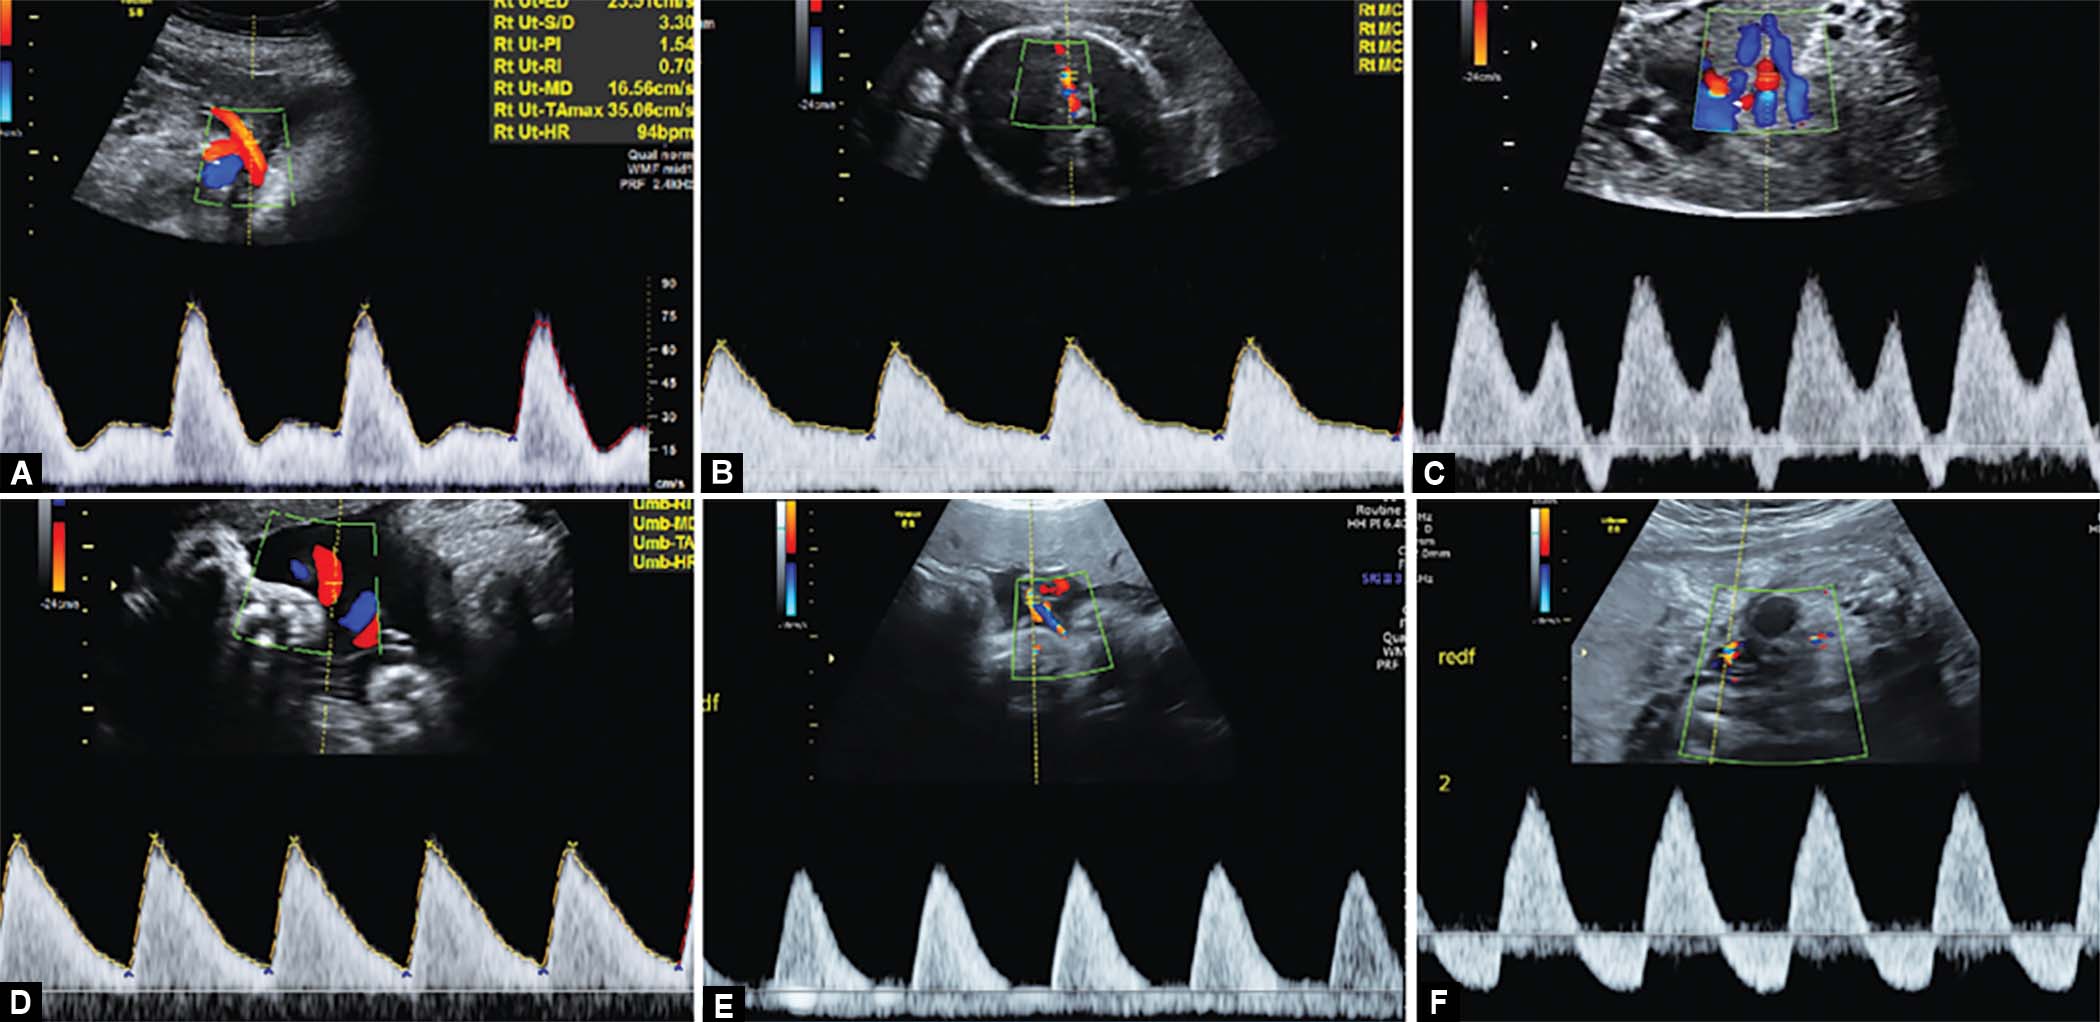

The following variables were assessed at each scan—fetal heart rate, presentation and lie, amniotic fluid index (AFI), placenta, fetal biometry HC/AC/FL, estimated fetal weight, and multivessel Doppler which includes assessment of uterine artery PI,15 umbilical artery PI,15 middle cerebral artery PI, C/P ratio, aortic isthmus waveform,16 ductus venosus PI15 (Figs 2 and 3 and Flowchart 1). All variables were measured as per the International Society of Ultrasound in Obstetrics & Gynecology (ISUOG) guidelines.17

Figs 2A to E: Normal uterine artery Doppler, normal umbilical artery Doppler, normal MCA Doppler, normal aortic isthmus Doppler, normal ductus venous Doppler

Figs 3A to F: Uterine artery Doppler with increased resistance, redistribution in MCA Doppler, ductus venosus Doppler with ‘a’ wave reversal, umbilical artery Doppler with increased resistance, AEDF in umbilical artery, REDF in umbilical artery